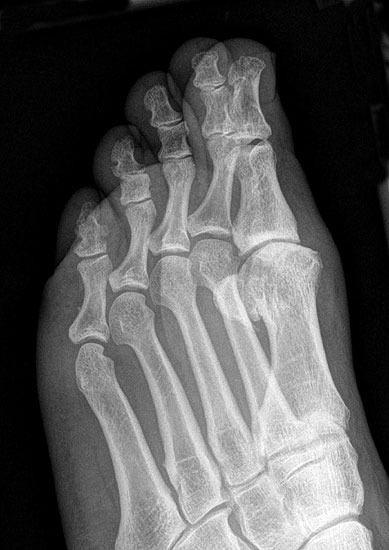

Klinisch zeigt sich stadienabhängig eine schmerzhafte Bewegungseinschränkung mit zunehmender Steifigkeit des Großzehengrundgelenkes. Vor allem die Einschränkung der Dorsalextension wird von den Patienten oft als unangenehm empfunden. Initial besteht eine bindegewebige Alteration im Gelenk, im weiteren Stadium treten Knorpeldegeneration und Begleitsynovialitis mit der Ausbildung von osteophytären Randanbauten auf. Klinische treten diese meist durch eine schmerzhafte dorsale Knochenkante in Erscheinung (Abbildung 1).

Im späten Stadium imponiert eine Gelenkblockierung durch freie Gelenkkörper. Während in den Anfangsstadien vor allem die dorsalen Anteile des Gelenks betroffen sind, betreffen die Veränderungen in den Fortgeschrittenen Stadien die gesamte Zirkumferenz einschließlich des Sesambeingleitlagers. Im Endstadium kommt es zu einer weitgehenden Ankylosierung des 1. Metatarsophalangealgelenks.

• Röntgenaufnahme des Fußes in drei Ebenen unter Belastung